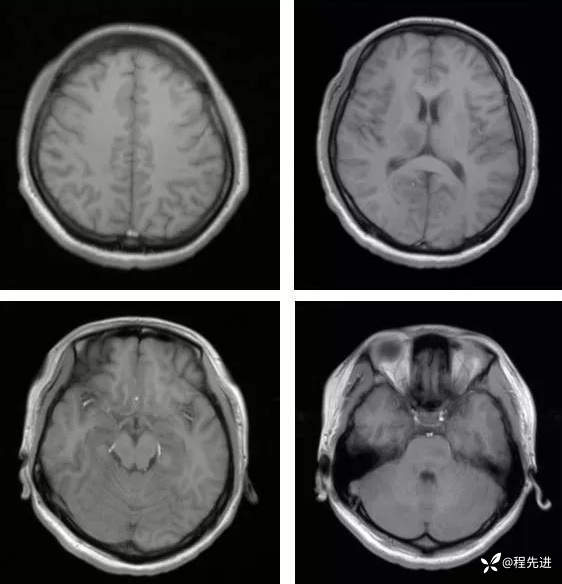

【神经】特别精彩病例|发热、头痛20天

主诉:发热、头痛20天

病史:患者20天前无明显诱因下出现畏寒、发热,热峰39.5℃,热型不规则,不伴咽痛,流涕,感头昏,有头痛,阵发性加剧,伴呕吐,为胃内容物非喷射性。患者在外院查头颅CT示:未提示异常。外院予以“头孢类、退热药”,无明显好转。我院急诊予以“泼尼松,热毒宁"治疗无明显好转